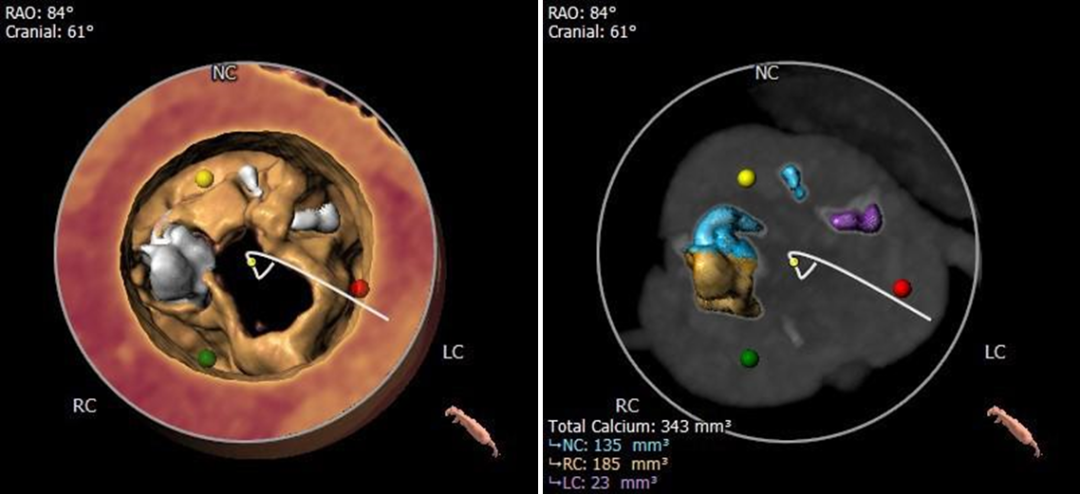

钙化分布

钙化主要分布于R-N之间,HU850 343mm³

冠脉测量

冠脉开口高度可,切线角度测量,

左窦瓣叶长于LCA开口到瓣叶根部距离

连续时相观察左窦瓣叶动度灵活,

收缩期瓣叶接近左冠开口高度;

3D打印模型22mm球囊扩张测试,左窦冗余空间小